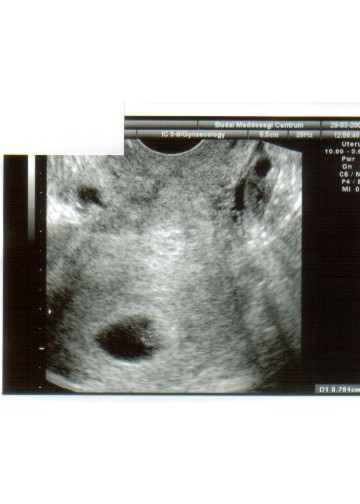

Első sztárfotónk!

Kép baboca

Kép

Hát ezen nem sok minden látszik, de rendben vagyunk.

Volt szívhang, 5 és fél hetesek vagyunk!

Merike, beteszel a kismamik közé?